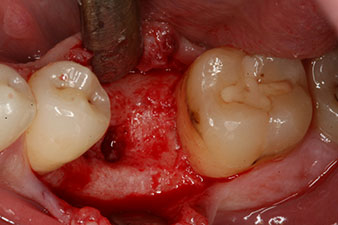

Cependant, six semaines après l’extraction on observe une ossification incomplète après la préparation du lambeau mucopériosté dans la région de l’ancienne alvéole mésiale.

L’implant a été posé comme prévu après élimination complète du tissu de granulation (blueSky, bredent).

Le couple utilisé pour la pose guidée était de 43 Ncm.

En outre, après avoir vissé une tige de mesure (SmartPeg) spécialement conçue pour l'implant, la valeur ISQ a été mesurée à l’aide de la sonde du module W&H Osstell ISQ.

Ce module est fourni en option avec l’Implantmed de W&H et est fixé au moteur d’implantologie (cf. Fig. 11). La valeur ISQ adimensionnelle mesurée immédiatement après l’insertion était de 64 dans l’axe oro-vestibulaire et de 68 dans l’axe mésio-distal (valeur maximale = 100).

Ces valeurs auraient pu indiquer une cicatrisation ouverte, voire une restauration immédiate. Étant donné le volume osseux crestal insuffisant au niveau de l’implant, une augmentation osseuse a été pratiquée localement à l’aide des fragments osseux recueillis lors de la préparation du lit implantaire, et des points de suture effectués pour éviter le contact de la salive.